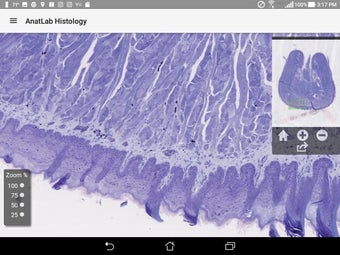

AnatLab Histology es una aplicación gratuita para Android desarrollada por Eolas Technologies Inc. que proporciona a los usuarios imágenes de diapositivas microscópicas de ultra alta resolución. Esta aplicación es una herramienta ideal para estudiantes, profesores, investigadores y el público en general. Con esta aplicación, pueden explorar el paisaje microscópico completo del cuerpo como si estuvieran mirando una colección de diapositivas reales en un microscopio físico. Tiene una función basada en la nube, la aplicación se puede acceder en cualquier dispositivo móvil Android, lo que la hace muy conveniente y accesible.

La aplicación ofrece una colección completa de imágenes de diapositivas microscópicas de histología que se pueden ver en ultra alta resolución. Las imágenes son de calidad excepcional y proporcionan una representación precisa del paisaje microscópico del cuerpo. La aplicación es fácil de usar y navegar, lo que permite a los usuarios explorar diferentes partes del cuerpo con facilidad.